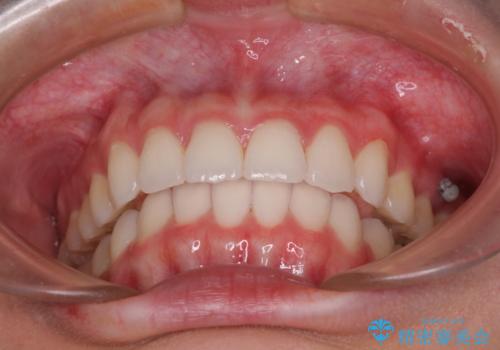

歯と歯の間を削ることで、飛び出した前歯が引っ込み、スッキリとした口元となりました。

歯の黄ばみも改善され、明るい歯並びとなりました。